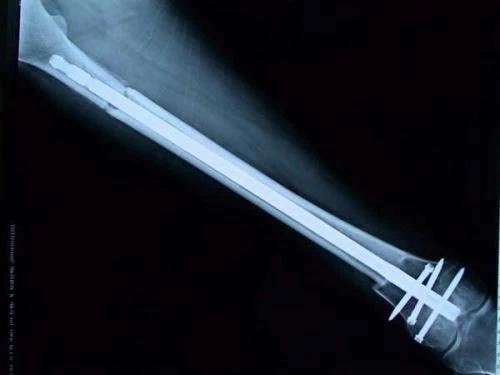

骨肉瘤是最常見的骨原發(fā)性惡性骨腫瘤,好發(fā)于兒童和青少年,四肢為其主要發(fā)病部位。目前,保肢治療被認為是肢體骨肉瘤的標準治療方法以及有效的基礎治療手段。我國幅員遼闊,但醫(yī)療技術發(fā)展不平衡,需要理論涵蓋充分、技術指導性強且適用于骨肉瘤治療領域的保肢治療指南。因此,“四肢骨肉瘤保肢治療指南”從保肢治療定義、手術方法、療效評估、術后處理與并發(fā)癥防治、康復指導與隨訪建議等方面系統(tǒng)介紹四肢骨肉瘤保肢治療方法,為規(guī)范和推進保肢手術技術發(fā)展、提高保肢治療成功率保駕護航。

保肢治療指經(jīng)典型骨肉瘤在多學科團隊醫(yī)生共同努力下完成的新輔助化療、保肢手術和輔助化療等一系列治療總稱,其目的是在提高患者生存率的前提下,減少局部復發(fā)、盡量保留良好的肢體功能。肢體經(jīng)典型骨肉瘤保肢治療方法如下圖所示:

關于新輔助化療

新輔助化療的目的是盡早殺滅遠處微小轉(zhuǎn)移灶,縮小腫瘤及周圍炎性水腫反應區(qū),以利于后續(xù)的保肢手術;觀察腫瘤對化療的敏感性,為進一步指定個體化的術后化療方案奠定基礎。骨肉瘤新輔助化療下的保肢治療如下圖所示:

新輔助化療藥物使用原則為:序貫用藥或聯(lián)合用藥,每個患者至少要選用兩種以上藥物,根據(jù)藥物說明書,靜脈或動脈給藥。初次用藥按照標準方案的藥物劑量計算給藥劑量。盡量維持總的藥物劑量強度。在嚴密觀察化療效果的前提下,建議至少用藥2個周期;根據(jù)所選用的標準方案要求間隔用藥。

洛鉑作為最新第三代鉑類藥物,憑借其穩(wěn)定性好、抗癌譜廣、抗瘤活性強以及既往臨床研究已顯示含洛鉑的新輔助化療方案的有效性和安全性,在“四肢骨肉瘤保肢治療指南”中作為一線新輔助化療藥物被推薦!